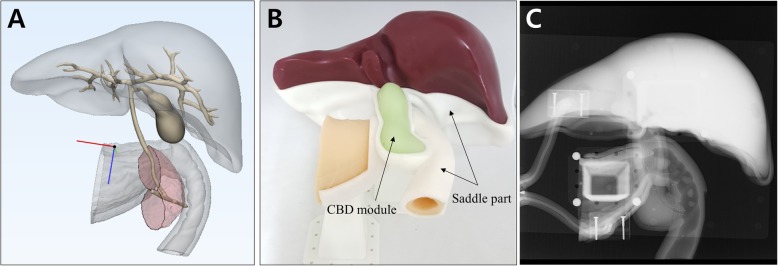

Digital 3D models of stomach and duodenum were obtained by importing the CT image data to the in-house software by StereoLithography (STL) file format. In addition, a hepatobiliary system, consisting of the ampulla of Vater, pancreatic duct with pancreas, common bile duct (CBD), gallbladder, liver, and intrahepatic bile ducts, was implemented in three dimensions using two open source programs of MeshLab and MeshMixer (Fig. 1a). In this study, endoscopic training in various anatomy of the ampulla of Vater and CBD had to be emphasized. Therefore, removable ampullary and CBD modules were mounted on the base of phantom (Fig. 1b and c). For performing different therapeutic procedures, eight different types of ampullary and CBD modules were separately designed to be utilized and repeatedly replaced on the base of phantom (Figs. 2 and 3).

For ERCP training, it is important to acquire real-time fluoroscopic images as well as endoscopic images. We fixed the ERCP phantom with a supporting stand, also made by the 3D printing technique, in the prone position as in a common ERCP procedure position (Fig. 1b). Because the shortening step was omitted during duodenoscope insertion into the area of ampulla, and the phantom was inversely located on the fluoroscopy table, it was necessary to adjust the direction of the fluoroscopic imaging (Fig. 4). It was not necessary to adjust the direction of endoscopic imaging.